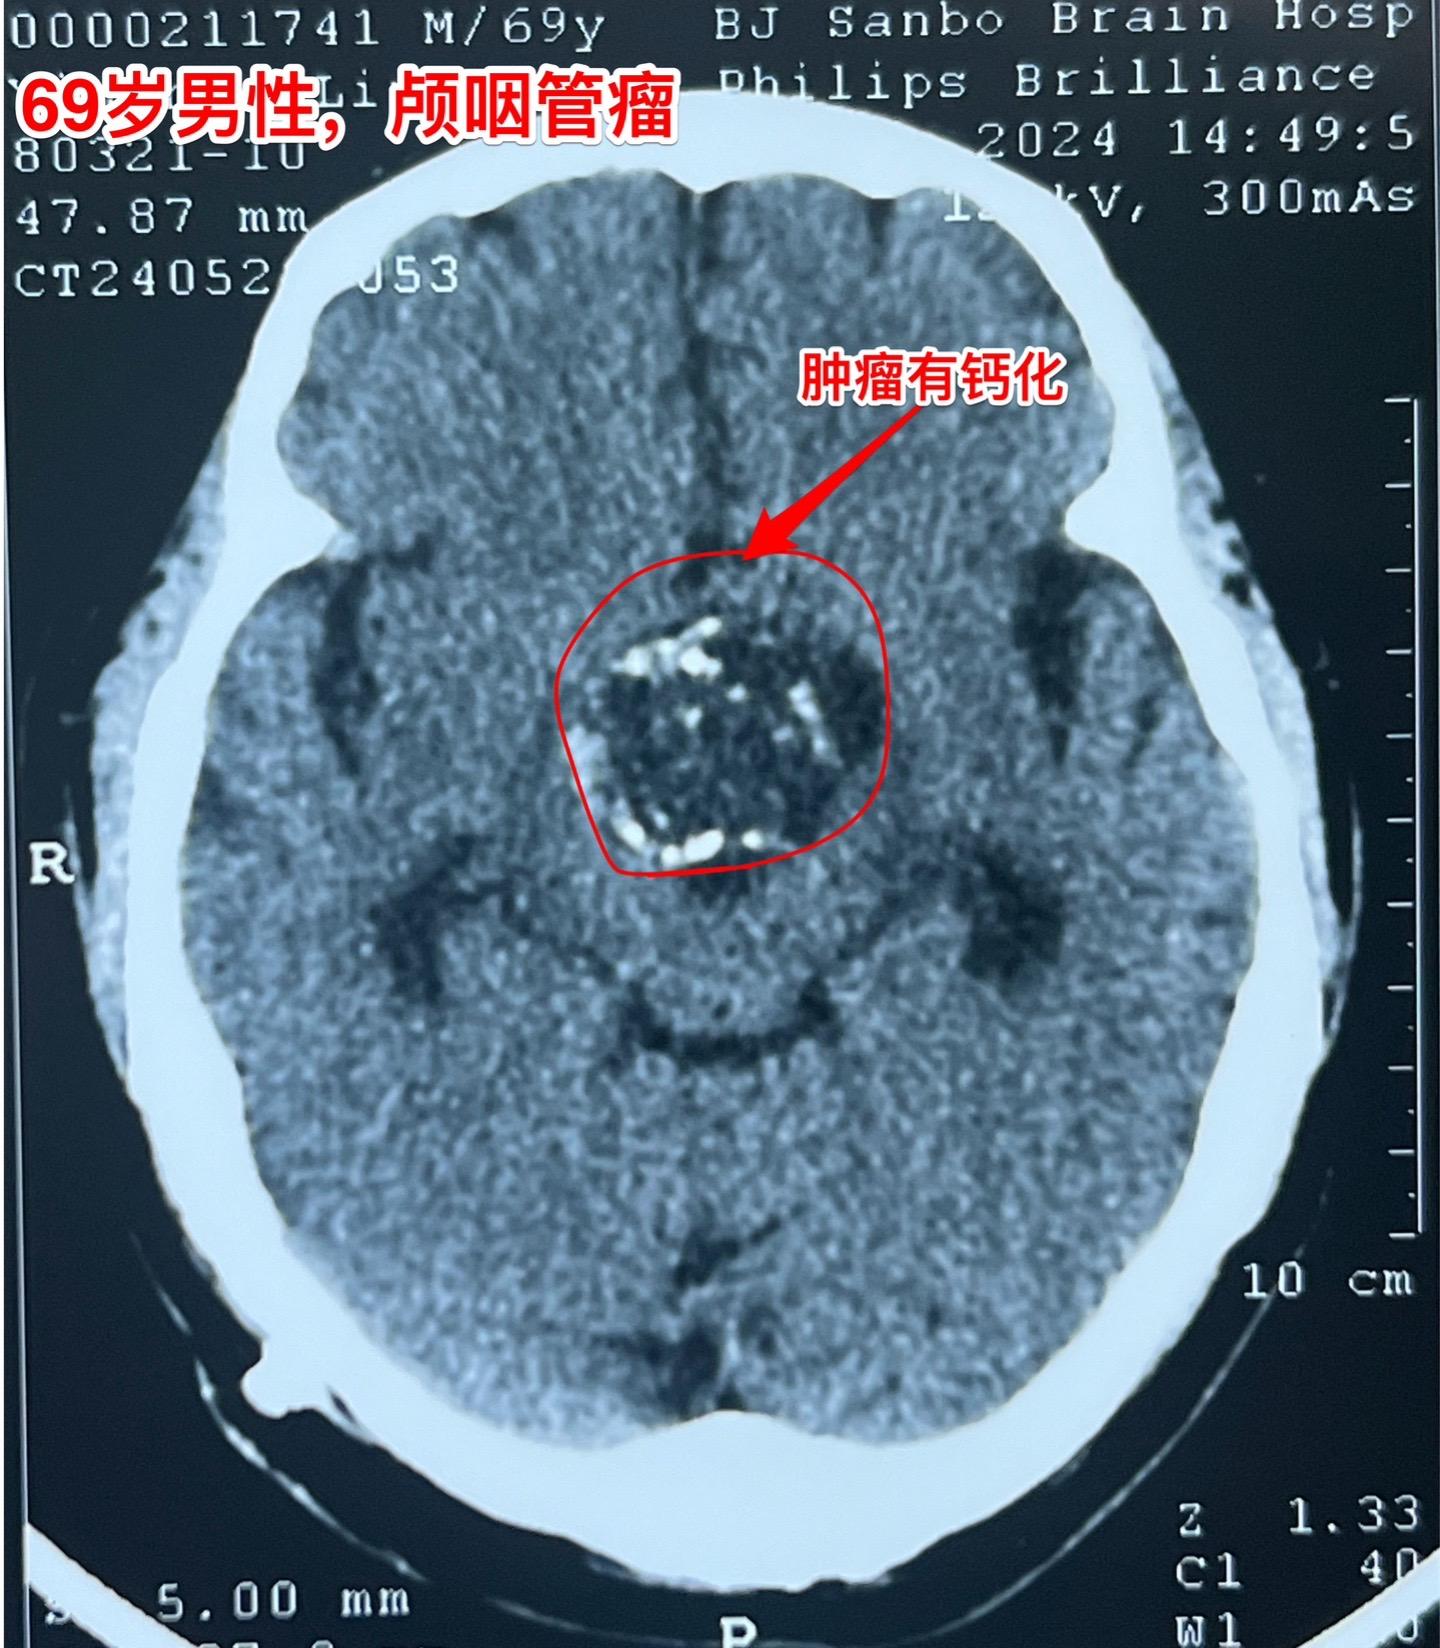

69岁发现颅咽管瘤还能作手术吗?69岁的南通市老人近半年出现记忆力差、糊涂。4月份出现尿失禁,到医院检查才发现病根儿是颅咽管瘤,肿瘤体积大,导致了脑积水。第一步在当地医院先作了脑室-腹腔分流术,治疗脑积水,尿失禁的症状有改善。 但是老人的身体很虚弱。还不能下地行走。这样的身体状态是不能承受切除颅咽管瘤这样的大手术的。 老人的女儿随后和我加后,我给予老人补充激素后,老人的身体状况才逐步改善,慢慢地能下地走路了。 不能不佩服这家人的勇气和爱心[强][强]!